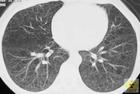

細胞構築學(cytoarchitectonics)是研究機體細胞組織和結構的一門學科。它揭示中樞神經系內神經元胞體大小和種類及胞體群的配布安排。

經研究,大腦皮質的古、舊皮質具有三層結構;新皮質具有六層結構,因不同腦區而有差異。

上丘(頂蓋)細胞構築分層自表到里為帶狀層、淺灰層、視層和丘系層。小腦皮質細胞構築分3層,由表到里為分子層、普肯野氏細胞層和顆粒細胞層。外側膝狀體背側核的細胞構築從腹到背分六層,1層、2層為大細胞,3層至6層為小細胞。